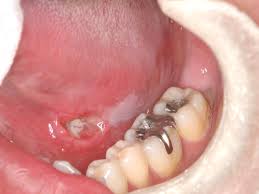

- 구강 위생 불량: 치주질환이나 만성적인 구강 염증은 암 발생 위험을 증가시킬 수 있습니다.

- 입안의 궤양: 2주 이상 지속되는 통증 없는 궤양

- 구강 내 혹이나 덩어리: 만져지는 종괴